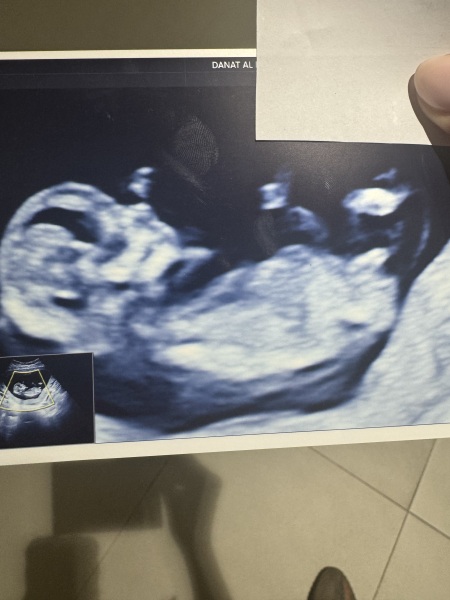

Nub Theory 12 weeks 3 days

Any guesses?

I would say girl!

Girl